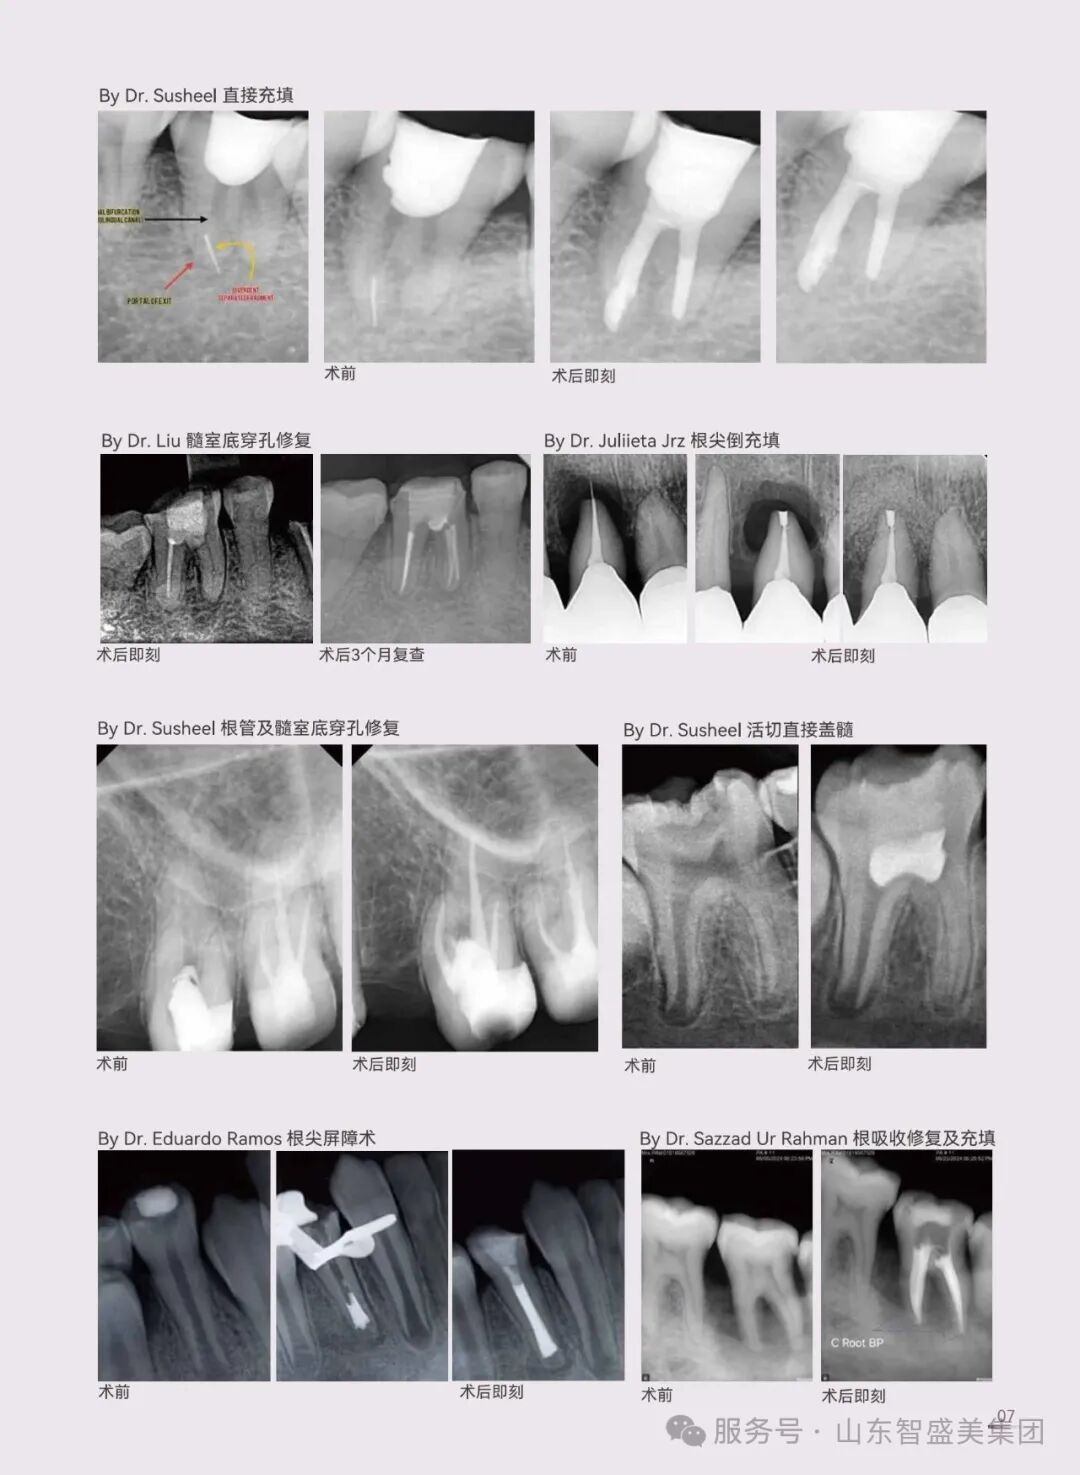

根管填充/修复